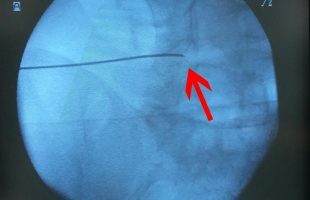

Η Ρομποτική Χειρουργική ενισχυόμενη από την Τεχνητή Νοημοσύνη αποτελεί μεγάλη εξέλιξη στη θεραπευτική αγωγή. Ο συνδυασμός αυτών συμβάλει ουσιαστικά: α. Στον προεγχειρητικό σχεδιασμό β. Στην επιτέλεση της χειρουργικής πράξης με την μέγιστη δυνατή ακρίβεια γ. Στη μείωση των επιπλοκών δ. Στην μείωση του χειρουργικού χρόνου ε. Στον ουσιαστικό περιορισμό της προσλαμβανόμενης ακτινοβολίας από το προσωπικό